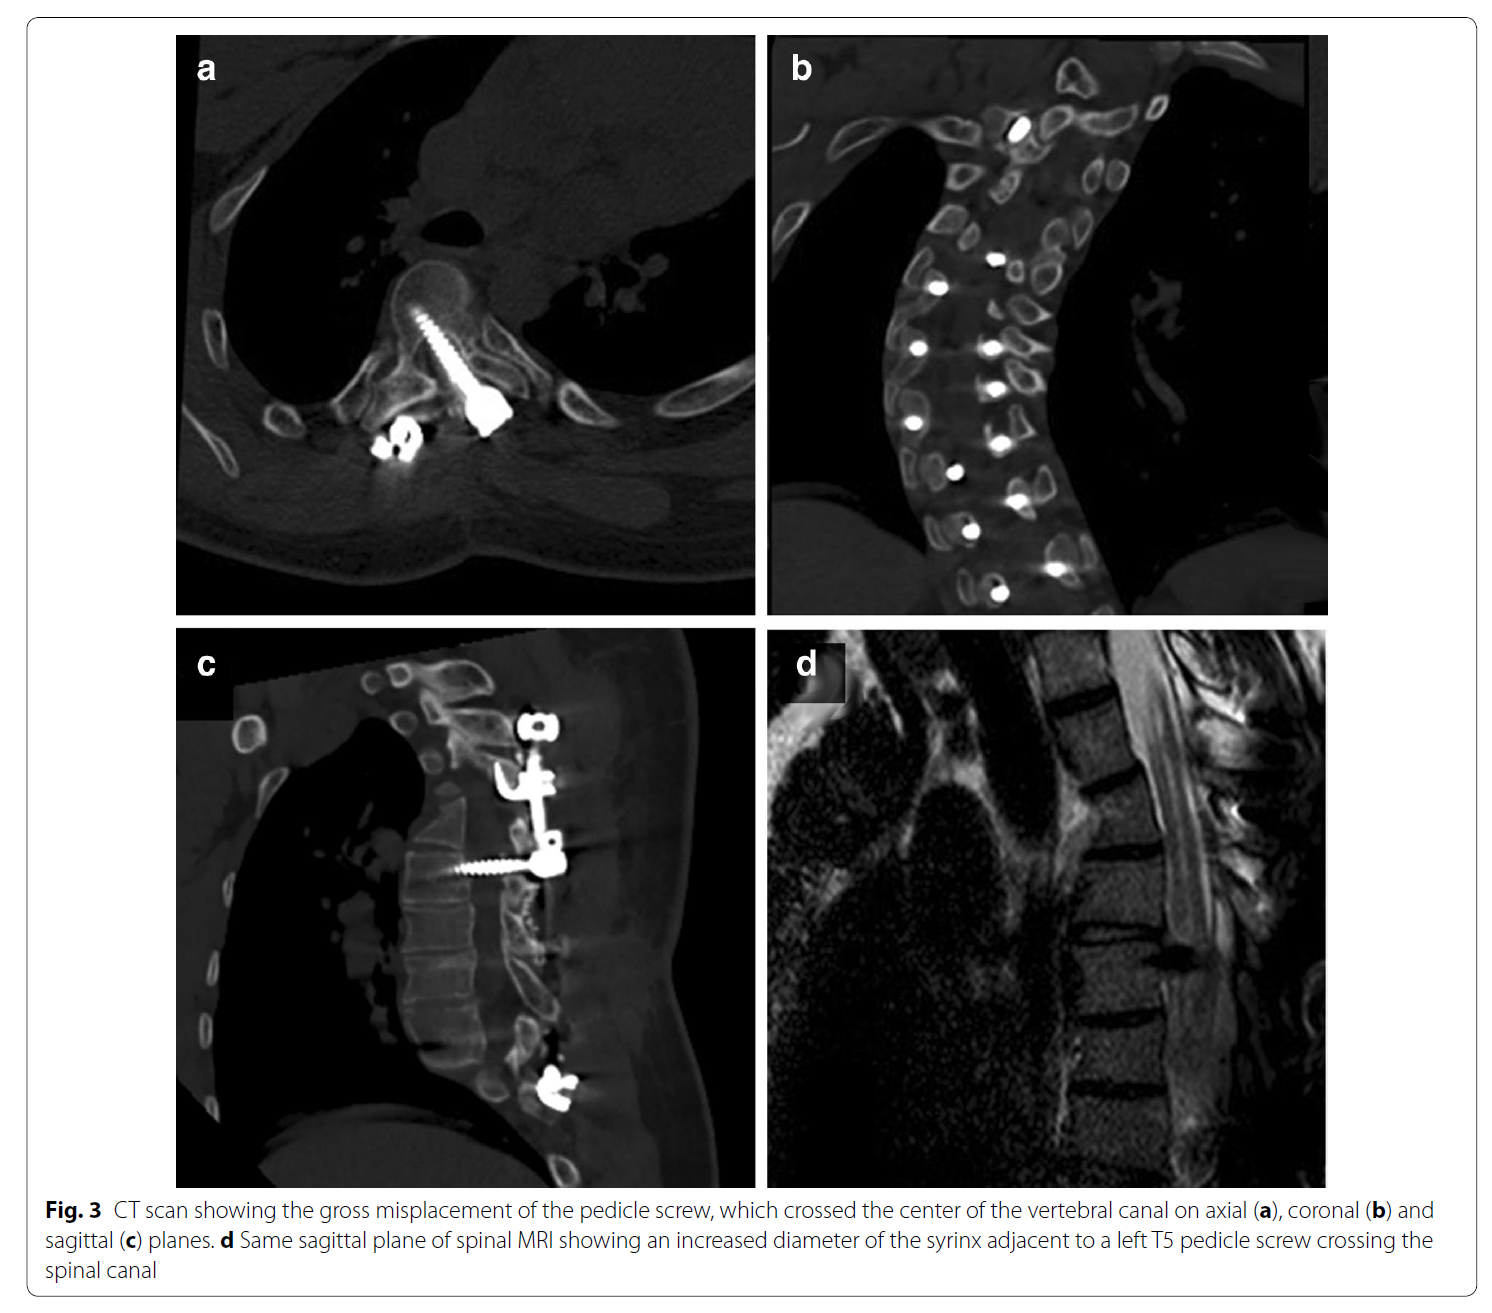

椎弓根钉误置引起的迟发性术后神经损害

椎弓根钉准确性的CT评价方法主要有如下几种。置钉失败可造成灾难性的后果,估计大家都听过坊间传闻:那个医院钉子打穿了主动脉,那个大腕钉子打瘫了脊髓。打瘫了基本上麻醉醒了就知道了,很少发生钉子碰到脊髓慢慢发生神经症状的情况。